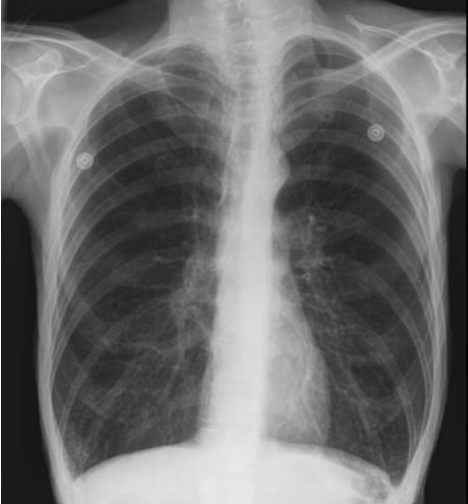

Bronchospasm usually presents with audible wheezing that can often be heard even without the aid of a stethoscope. There is a delayed expiration phase and the patient has obvious difficulty expelling the air during exhalation. The chest is hyper-inflated and the jugular venous pressure is elevated. The wheezing is bilateral and desaturation on pulse oximetry is usually not a prominent feature. Shortness of breath in asthma is a very subjective symptom and a peek flow meter should be used to assess the severity of the attack. The peak flow meter readings should be evaluated in comparison to the patient's usual peak flows at home when he or she is well [6]. If the bronchospasm is severe then the intra-bronchial gas flow is greatly reduced, and the wheezing may be more difficult to identify. A capnography tracing shows an upslope during phase 3 absence of an and the end expiratory plateau (Figure 1). In a patient with the physical exam findings of peripheral edema, auscultation of crackles and a third heart sound, and a low pulse-oximetry saturation, the diagnosis is likely to be pulmonary edema rather than bronchospasm. The chest X-ray will clearly distinguish between these two conditions. With bronchospasm, the lung fields are hyper-expanded and the heart will be compressed into a tubular shape (Figure 2). In contrast, with pulmonary edema, the heart is often enlarged and the lung fields are opaque and show a characteristic bat's wing appearance.

Figure 2: Representative chest X-ray of bronchospasm. During acute bronchospasm there is hyperinflation of the lungs with compression of the heart into a tubular shape and displacement of the diaphragm in a caudal direction. The increase in intrapulmonary pressure may lead to decreased venous return to the heart and a decrease in cardiac output.